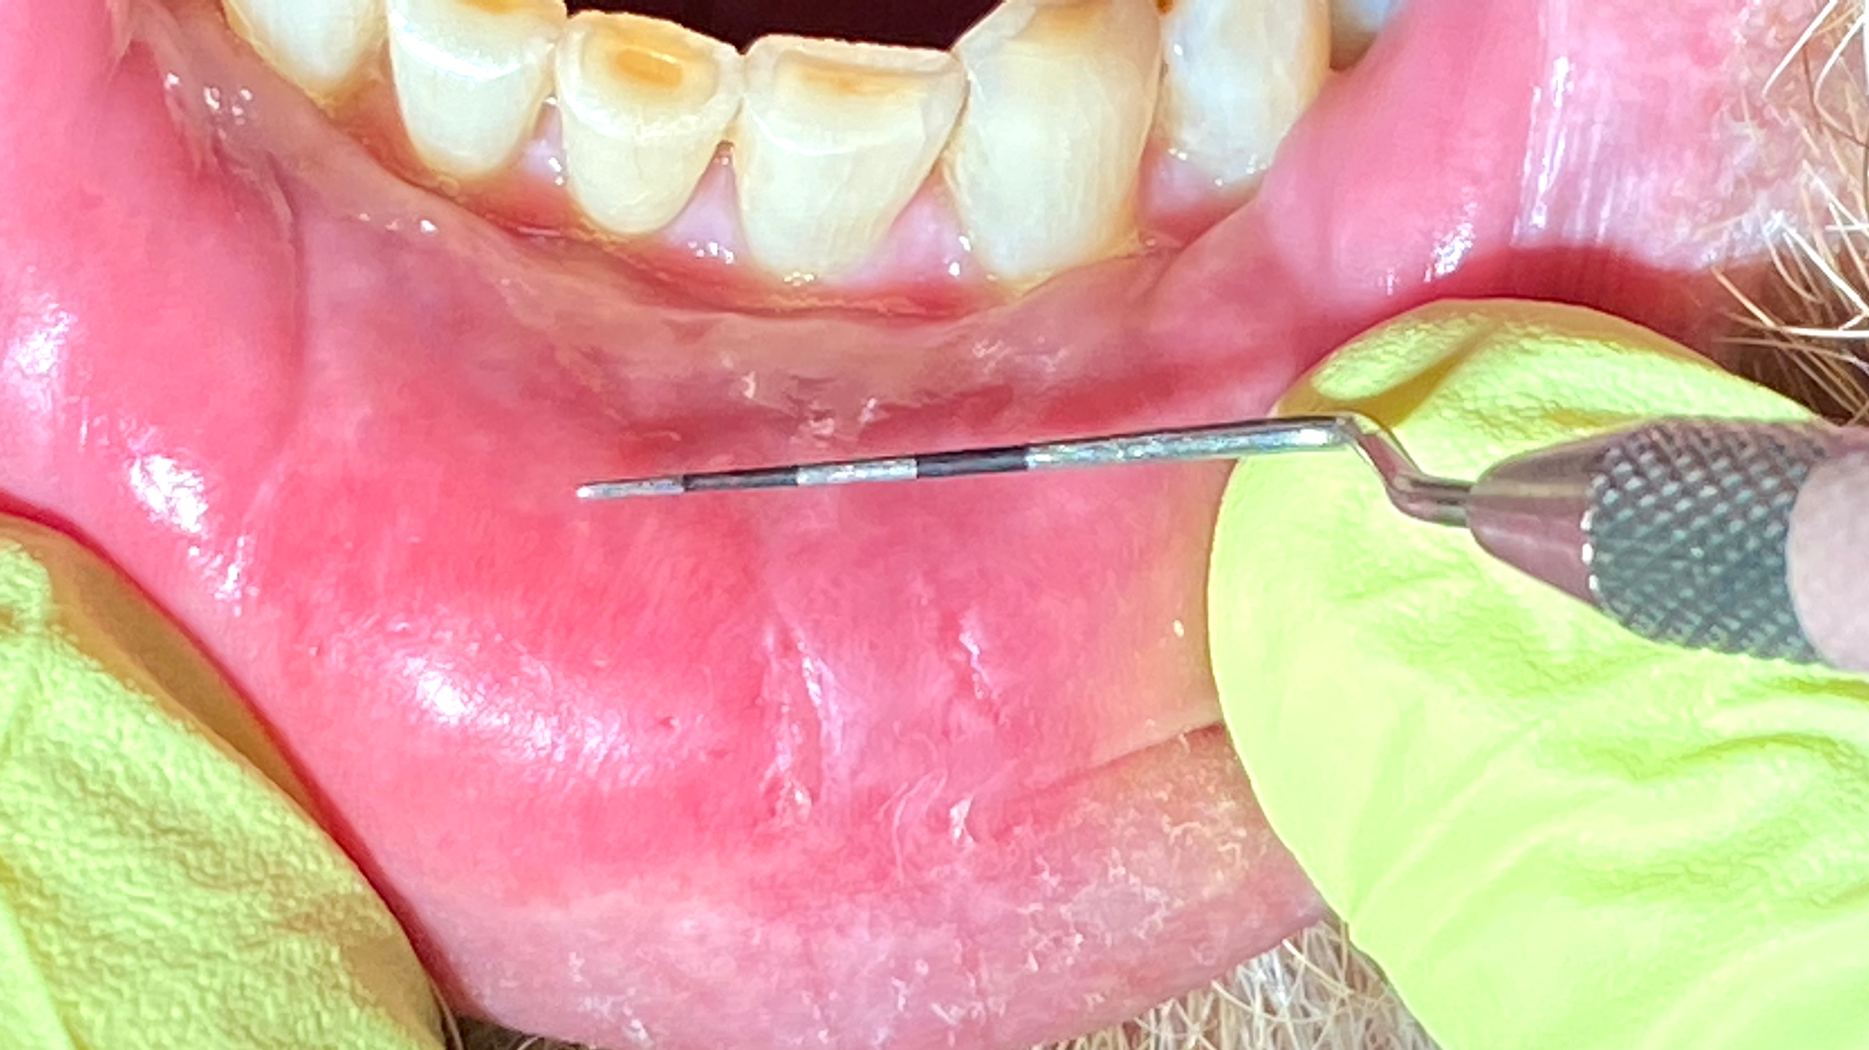

As I suspected, the initial diagnosis for this patient was lichen planus (LP) with ulcerative tendencies, even though there were no real prominent ulcers presenting at the time. The burning in the mouth that the patient was experiencing was more or less what initiated suspicion of the diagnosis.

Here’s a quick refresher on lichen planus. LP is an inflammatory condition that affects the mucus membranes of the mouth. Symptoms of burning, itching, pain, and overall discomfort can range from mild to severe. LP is a T-cell autoimmune disease commonly found in the fourth decade of life, and it affects men more than women.1 The buccal mucosa, tongue, and gingiva are the most common oral areas affected.1